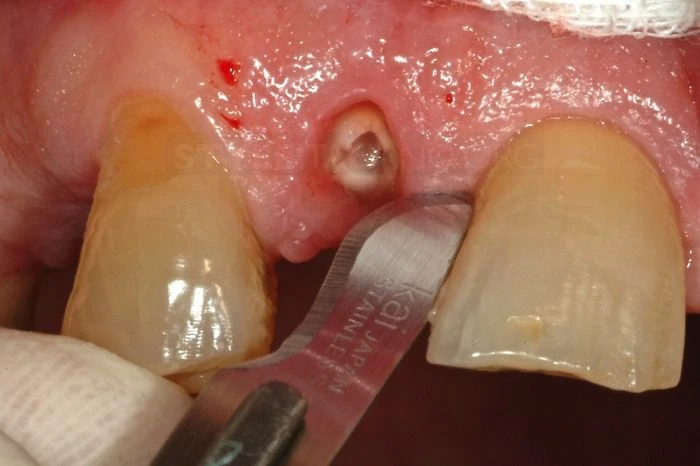

Phần răng bị gãy phải được ngâm trong nước muối sinh lý (0.9% NACl) tương tự như khi xử lý một chiếc răng gãy chân khác, chúng ta không được đánh bóng vết nứt hay răng để tạo điều kiện dán dính tốt hơn(6). Quan sát mảnh răng gãy có thể thấy bề mặt vết gãy bị vát ít nhất là 3mm về phía chóp so với mặt trong.

Hình dạng vết gãy thế này làm cho việc cách ly để điều trị tủy và gắn răng trở lên rất phức tạp.

Nhìn từ mặt bên

Vì những khó khăn do vết gãy gây ra các bác sĩ quyết định tạo một đường rạch trong rãnh lợi bằng dao phẫu thuật 5c

Cắt nhú lợi ngoài về phía cuống răng để bảo tồn đám rối mạch máu vùng lợi kẽ răng.